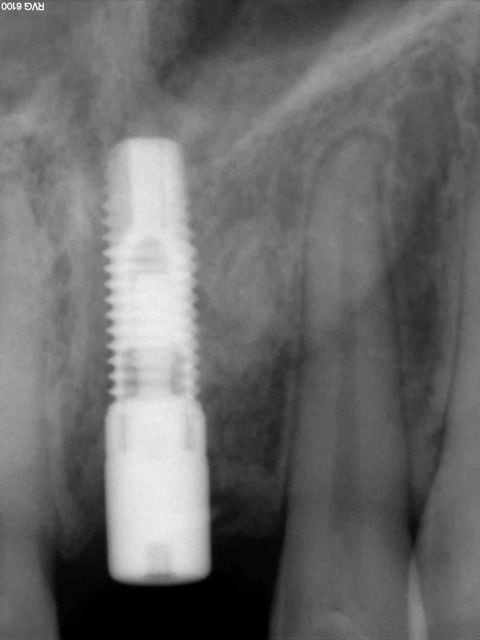

nobel effectivement: RP Replace Groovy 4*13

Non pas speedy mais straight: apex moins agressif et implant moins compressif

J'ai eu beaucoup de craterisation avec le speedy ( surtout sur des sites anciens ) et sur une greffe je préfère la mise en place plus douce du straight pour ne pas risquer de 'décoller' le greffon cortical